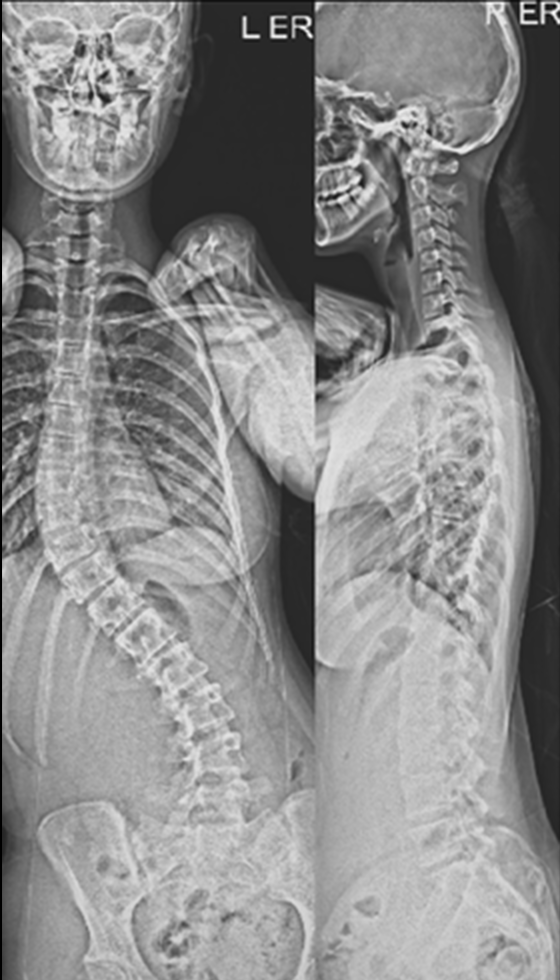

The procedure involves repositioning the spine and securing it with Screws and Rods. Bone graft is then placed so the treated vertebrae gradually heal together into one solid segment. This creates long-term stability, preventing further curve progression and improving overall alignment.

Gallery : Before - After

After

Before